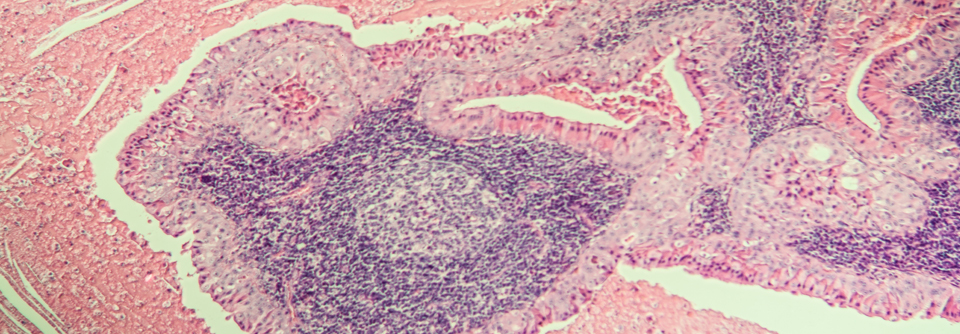

Rektumkarzinom: Bestrahlung, Chemo und Geduld könnten Operation ersparen

Tumorkontrolle, Überleben und Lebensqualität verbessern – das sind die Ziele beim lokal fortgeschrittenen Rektumkarzinom. Inwiefern das mittels…

mehr

Onkologie und Hämatologie , Gastroenterologie ASCO 2021